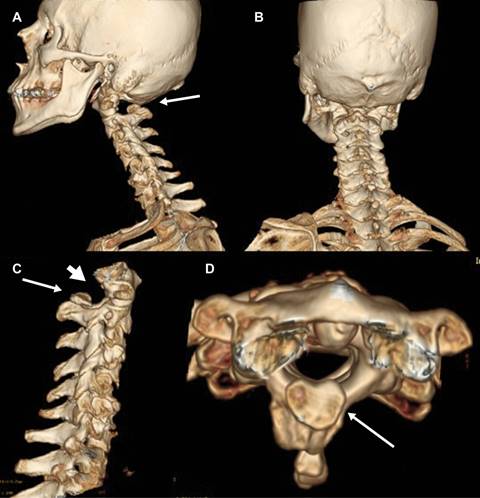

La clasificación de los defectos del arco posterior del atlas efectuada por Currarino7 (Figura 4) indica que existen cinco diferentes tipos de anomalía (Figura 5), siendo más frecuente la tipo A en más de 95% de los casos, el caso que se presenta se catalogó de tipo D por la ausencia de hemiarcos posteriores con presencia de tubérculo posterior.

Figura 5: Imágenes tomográficas con reconstrucción 3D de columna cervical en diferentes proyecciones, que muestran la ausencia del arco posterior del atlas, con persistencia del tubérculo posterior.